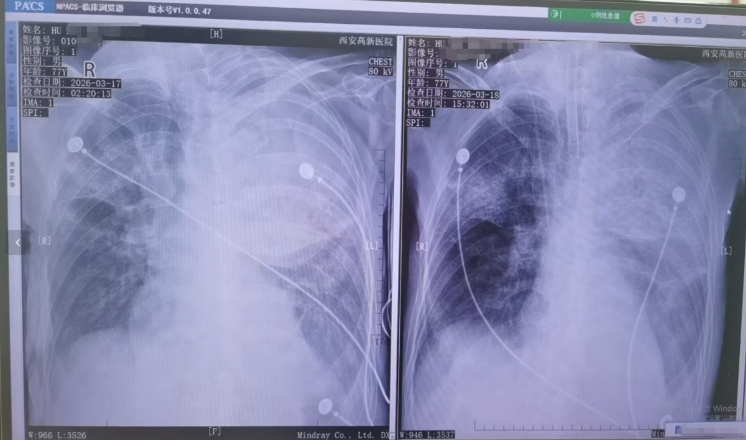

图片▲患者胸片

胡先生说,起初以为是感冒,住院治疗没有效果,还越来越严重,以至于病情危重,“整个肺部全白了”,并且出现呼吸衰竭,医院甚至下了病危通知书。3月17日,家人赶紧将父亲转院到西安高新医院抢救,到医院以后就住进了ICU。经检查,才发现是鹦鹉热衣原体感染导致的重症肺炎。胡先生提供的一份《西安高新医院诊断证明》显示,胡先生的父亲3月17日以重度肺炎入院。诊断为重症肺炎(鹦鹉热衣原体感染)I型呼吸衰竭,急性呼吸窘迫综合征,脓毒症等。